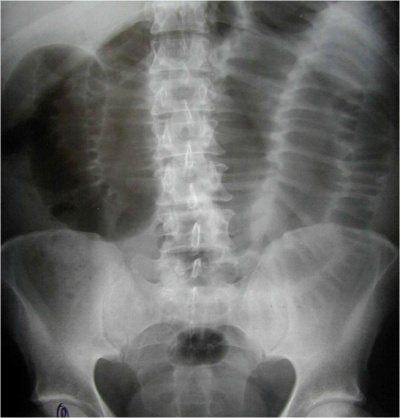

בצילום בטן סקירה ניתן לראות חסימות דינמיות, התרחבות של המעי הדק (תצלום 1.4), ופלסי אוויר נוזל במרכז הבטן המסודרים בצורת מדרגות (תצלום 2.4). הוולבולה קוניובנטס מודגשים לרוחב הרירית (תצלום 3.4).